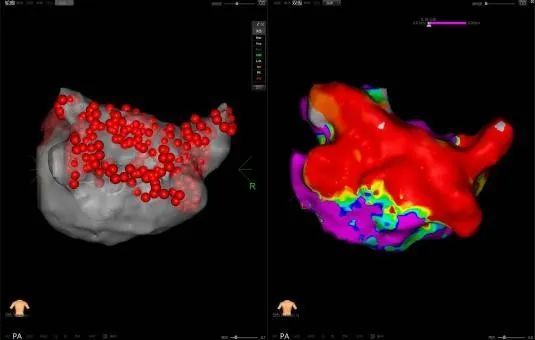

PFA是一种创新且有前景的微创、安全和高效的新兴治疗方法,通过瞬时的高电压脉冲电场直接作用于心肌细胞,以不可逆电穿孔机制消融心脏组织,有效的隔绝异常激动及异位传导路径,从而恢复正常心律。PFA具有独特的消融组织选择性、消融时间极短、无热损伤炎性水肿和附带周围组织损伤并发症等特点,是现有技术中针对心律失常更理想的消融手段,可大大减少因传统消融存在手术并发症风险及消融不足导致房颤复发的风险。与传统的射频导管消融或冷冻球囊消融相比,脉冲电场消融手术具有更加安全、消融效率高、并发症少等诸多优点,彻底改变了房颤治疗的格局,为房颤患者带来更好的治疗方案,带来更多治愈的希望。

此次手术患者均为持续性房颤患者,由延安大学咸阳医院吴栋梁院长、心律失常专家刘雄涛副院长带领介入团队开展,安全高效、圆满完成手术,手术过程患者全程清醒,术中自诉感觉良好,无痛苦感受。术后患者的心律恢复并维持了窦律,目前恢复情况良好,无任何并发症出现。